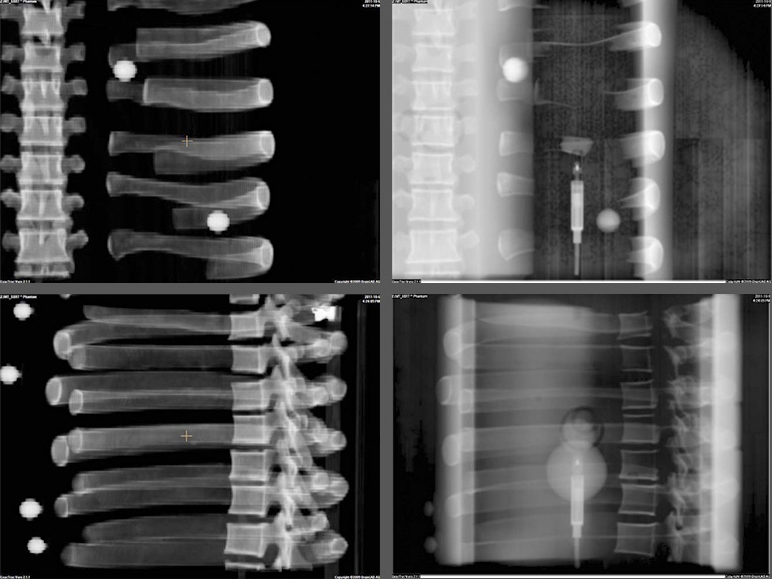

The End-to-End SBRT Phantom is a single tool for high-accuracy end-to-end commissioning and routine QA necessary for the high dose per fraction associated with SBRT deliveries.

Linear attenuations of the simulated tissues are within 1% of actual attenuation for water and bone, and within 3% for lung from 50 keV to 15 MeV. The phantom contains a 3D anthropomorphic removable spine with cortical and trabecular bone as internal landmarks

The E2E SBRT Phantom contains multiple targets and alignment marks for verifying that imaging, localization, and targeting systems are aligned. This is a critical need for accurate delivery of these high-dose treatments.

Three OSL pockets in the right lung provide high-resolution dosimetry measurements to the target and spinal cord in a single delivery.

The removable split spine allows for film measurements in the sagittal orientation in the inferior half of the spine rod. Film can also be placed in the sagittal slice in the spine and lung inserts.